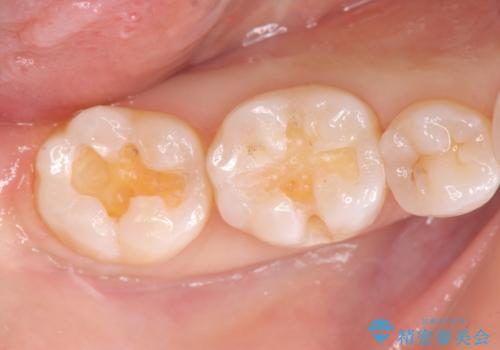

- 笑った時に見える銀歯を外したいと希望され来院されました。

銀歯の下には初期の虫歯も見られたので、除去後精密なシリコン印象を行いセラミックインレーを製作しました。

審美性を回復し、虫歯も予防のできる精密なセラミックインレーを装着することができました。